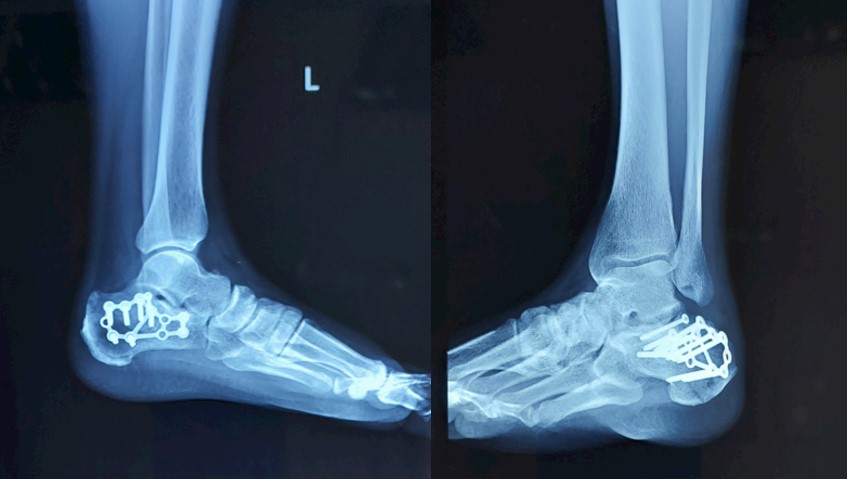

Відкрита репозиція та внутрішня фіксація за допомогою МОС — так красиво звучить назва того, що насправді є тривалою, кропіткою битвою за кожен міліметр. Хірург збирає уламки, один за одним, повертає на місце, відновлює суглобову поверхню — вона має стати гладкою, як дзеркало, інакше майбутнє буде наповнене болем та артрозом.

Спеціальні пластини та гвинти — це арматура, що тримає відновлену конструкцію. Вони вживлюються у кістку, стають її частиною, екзо- та ендо- скелетом всередині кальцієвого. Це технологія та мистецтво одночасно. Операція може тривати години, кожен шматок має стати на своє місце, кожен гвинт вкручений під правильним кутом, щоб не заподіяти шкоди вже пошкодженим тканинам.

Черезшкірна фіксація переломів пʼяткової кістки — для тих випадків, коли перелом простіший, а ризики відкритої операції занадто великі. Крізь маленькі проколи, під контролем рентгену (ЕОП-у), хірург проводить гвинти, скріплюючи уламки без великих розрізів. Менша травма, швидше загоєння, але й можливості обмеженіші.